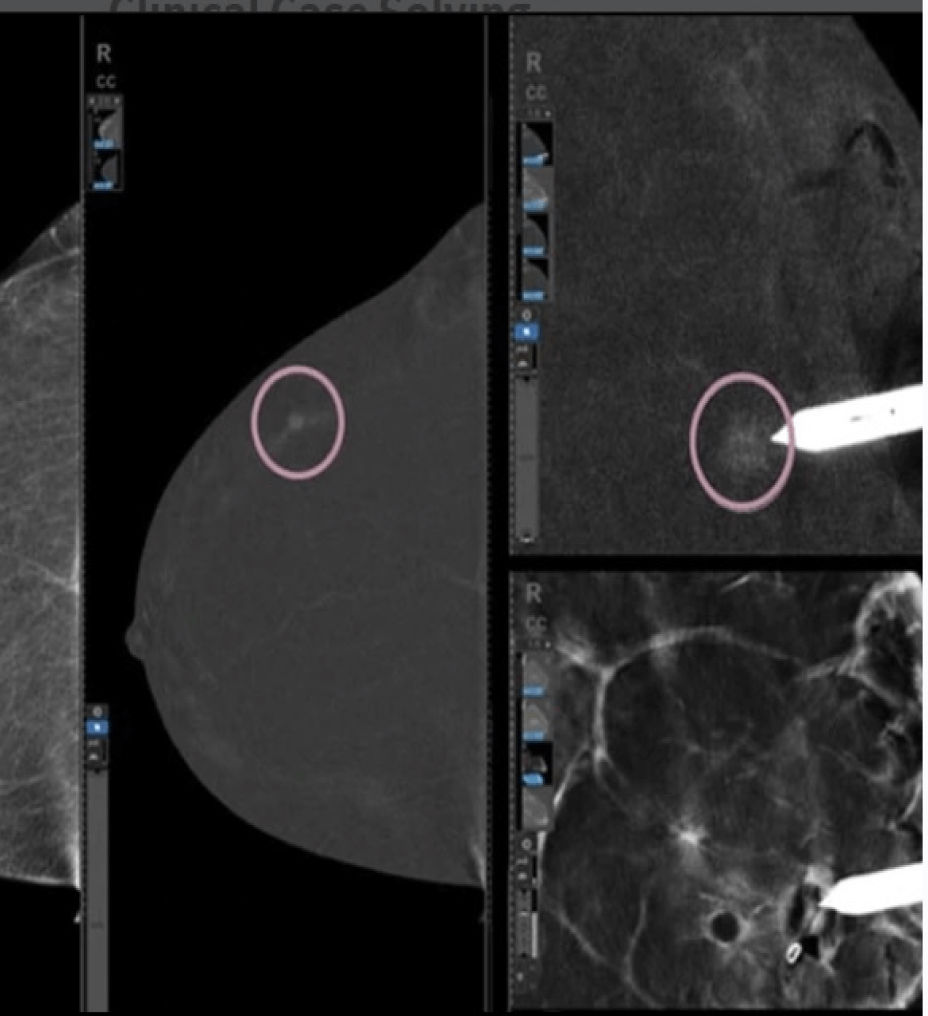

See and biopsy what matters

Serena Bright enables providers to see lesions using contrast-enhanced mammography (CEM) and sample with certainty. This allows patients to undergo breast biopsy exams using the same mammography equipment, in a familiar setting, with familiar staff, to help relieve some of the stress of a biopsy procedure.

Avoid the challenges of seeking correlating lesions in MRI. CEM allows you to see lesions clearly and sample with certainty with the same image guidance.

With high sensitivity and specificity, CEM helps drive accuracy in biopsy. It allows you to clearly target suspicious areas by correlating lesion locations already identified in your patient’s diagnostic enhanced mammogram.